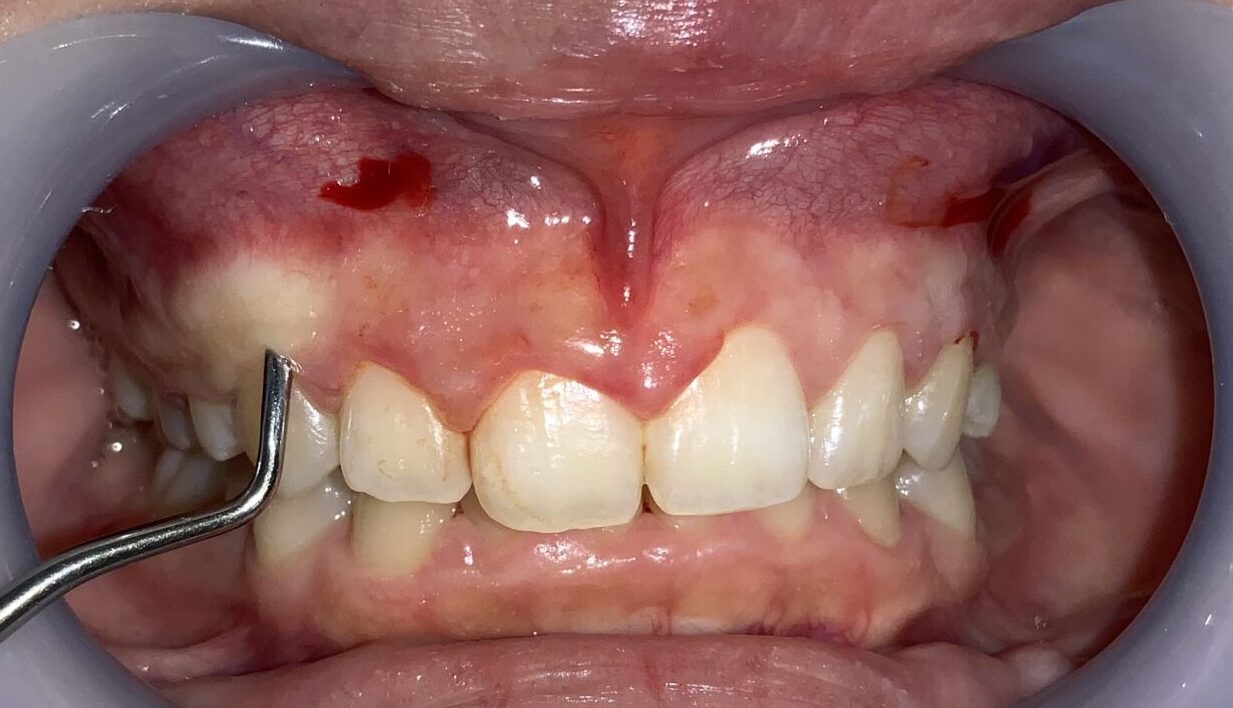

過蓋咬合(かがいこうごう)の状態です。上の歯並びが下の歯並びを大きく被せてしまい、上の歯並びに隠れてしまい下の前歯が全く見えません。

このような状態の場合には歯を支える歯槽骨がとがっていたり、ざらざらしてしまっている場合が多く、歯槽骨整形を併用しなければ、後戻りをしてしまう場合があります。

前歯の隣の歯です。

こちらの歯の歯ぐきも分厚くかぶさっているようです。

安全に切り取ることができる範囲がわかります。